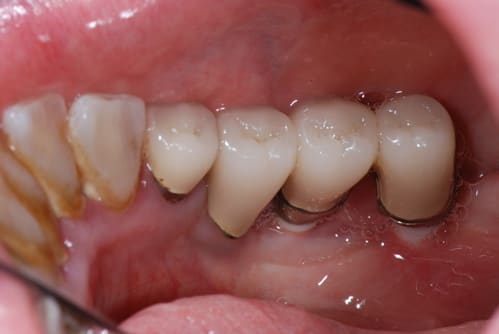

pour le débat, voici ce que j'ai posé en 1990, 1 TBR vissé + 2 zircones vissés de Sandhaus, et voici le résultat 17 ans plus tard. comme le mélange des genres va interpeller, j'explique. il s'agit là de la 2ème pose d'implant de ma carrière débutante, alors que je faisais le DU de la Salpétrière. c'était à l'époque où l'on débatait sur le risque de solidariser un implant à une dent. j'ai finalement préféré ne pas solidariser mes 2 implants 36-37 à la 34 et j'ai donc rajouté un implant en 35 par la suite; entre temps, j'avais abandonné les implants en zircone car la technique chirurgicale proposée avec ne me plaisait pas et que celle proposée pour les implants en titane me convenait davantage. il s'agissait déjà pour Sandhaus de poser les implants sans faire de lambeau et pour le débutant que j'étais, je trouvais ça trop délicat; j'ai donc terminé le cas avec un TBR en technique Branemark plus sécurisante.